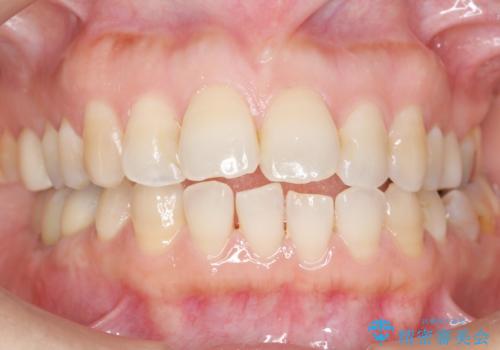

奥歯でしっかり噛むことができるようになり、喜んで頂けました。

セラミッククラウンの審美的な仕上がりにもご満足頂けました。